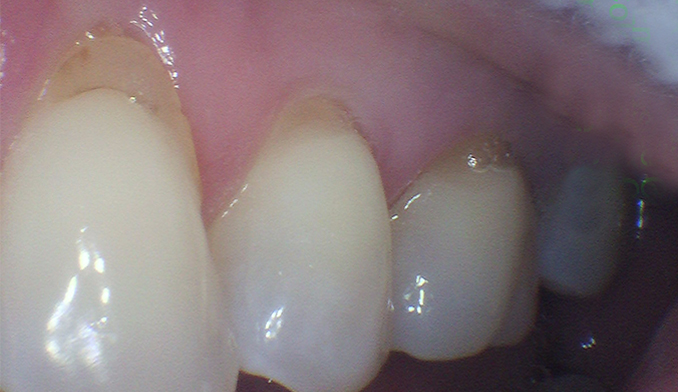

Front Tooth Repair with Bonding

The patient fractured her front tooth. We restored both the appearance and function of the tooth using cosmetic bonding, achieving a natural-looking and durable result.